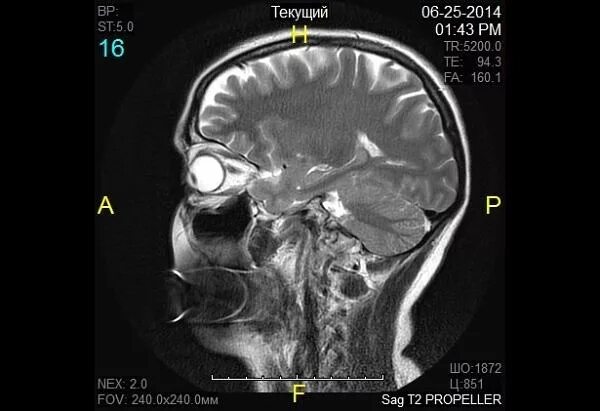

Мрт орбит и зрительных нервов